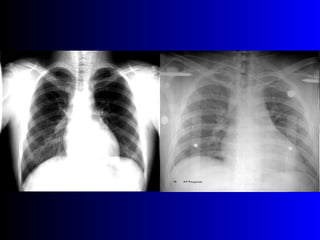

Este documento describe la técnica para realizar una telerradiografía de tórax normal e identifica las estructuras visibles en la imagen, incluyendo los huesos, vasos sanguíneos, grasa, tejido subcutáneo, pulmones y mediastino. Explica que es importante centrar la imagen en los ápices pulmonares, senos costodiafragmáticos e inspiración profunda para una visión clara de las estructuras.